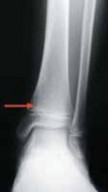

FIG 1•

Kump’s bump. The

arrow

demonstrates the central-medial–located Kump’s bump, which is where physeal closure begins. We believe that damage to this structure may induce premature physeal closure.

2. The distal tibial physis is for the most part transverse; however, there is an anterior medial undulation that consistently appears within the first 2 years of life that has been described by Kump (termed Kump’s bump). This central-medial location is where physiologic physeal closure begins (

FIG 1

).